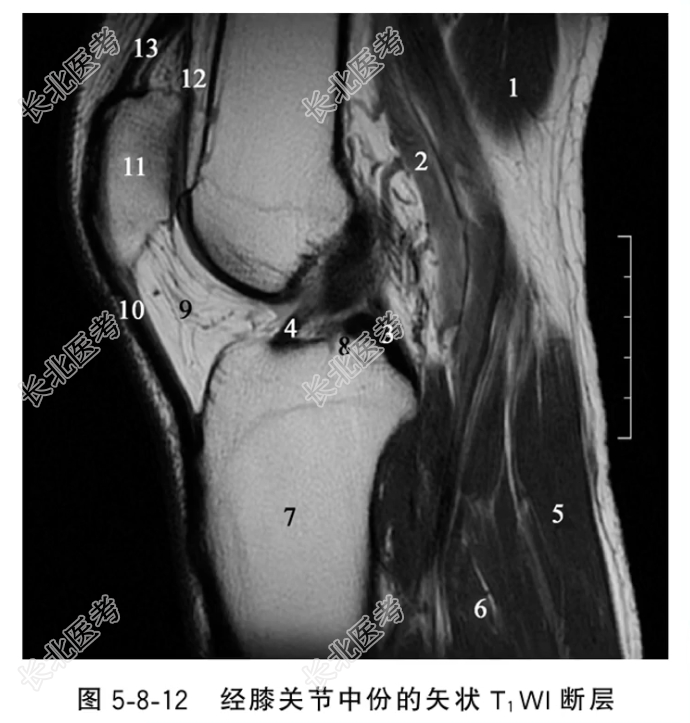

- 单项选择题在经膝关节中份的矢状T,WI断层图像中,标注3、4、12的结构分别是

A、后交叉韧带、前交叉韧带、髌上囊

B、前交叉韧带、后交叉韧带、髌上囊

C、后交叉韧带、前交叉韧带、髌下脂肪垫

D、前交叉韧带、后交叉韧带、髌下脂肪垫

E、后交叉韧带、髌上囊、前交叉韧带